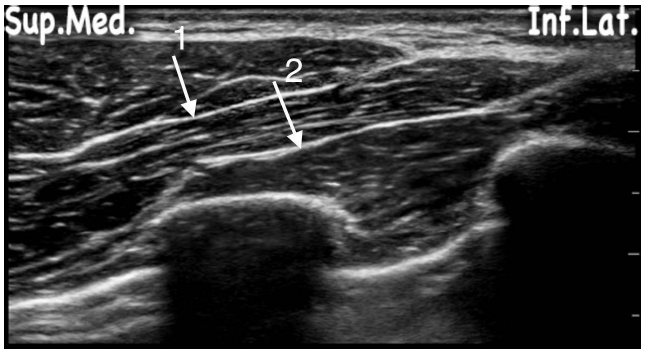

Observe a figura a seguir e assinale a alternativa CORRETA: